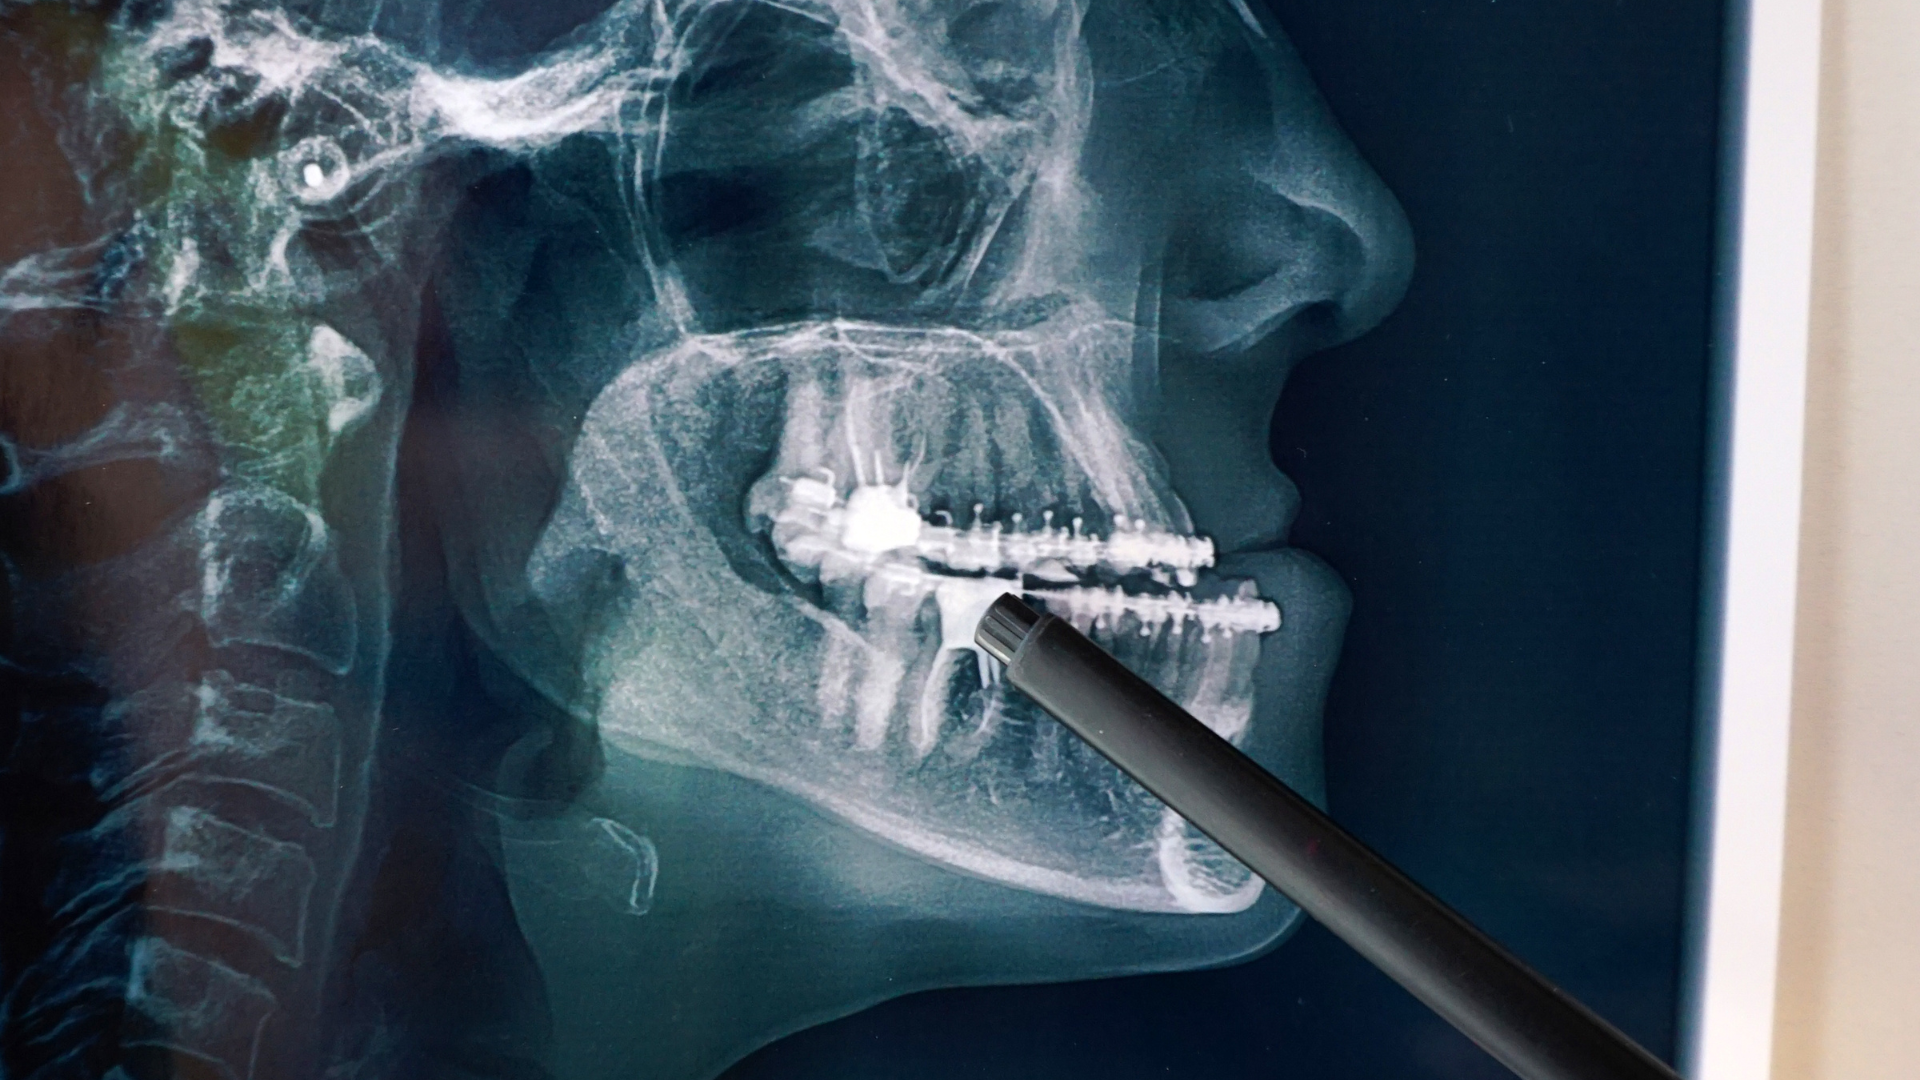

Chấn thương răng - hàm - mặt

Trong các trường hợp tai nạn, CT răng giúp:

- Phát hiện gãy chân răng.

- Gãy xương ổ răng hoặc xương hàm.

- Đánh giá mức độ di lệch và tổn thương phối hợp.

CT đặc biệt hữu ích khi tổn thương khó quan sát trên phim X-quang thường.

Đặc biệt trong các thủ thuật xâm lấn như nhổ răng khôn khó, cấy ghép implant hoặc phẫu thuật xương hàm, CT răng gần như là công cụ không thể thiếu.